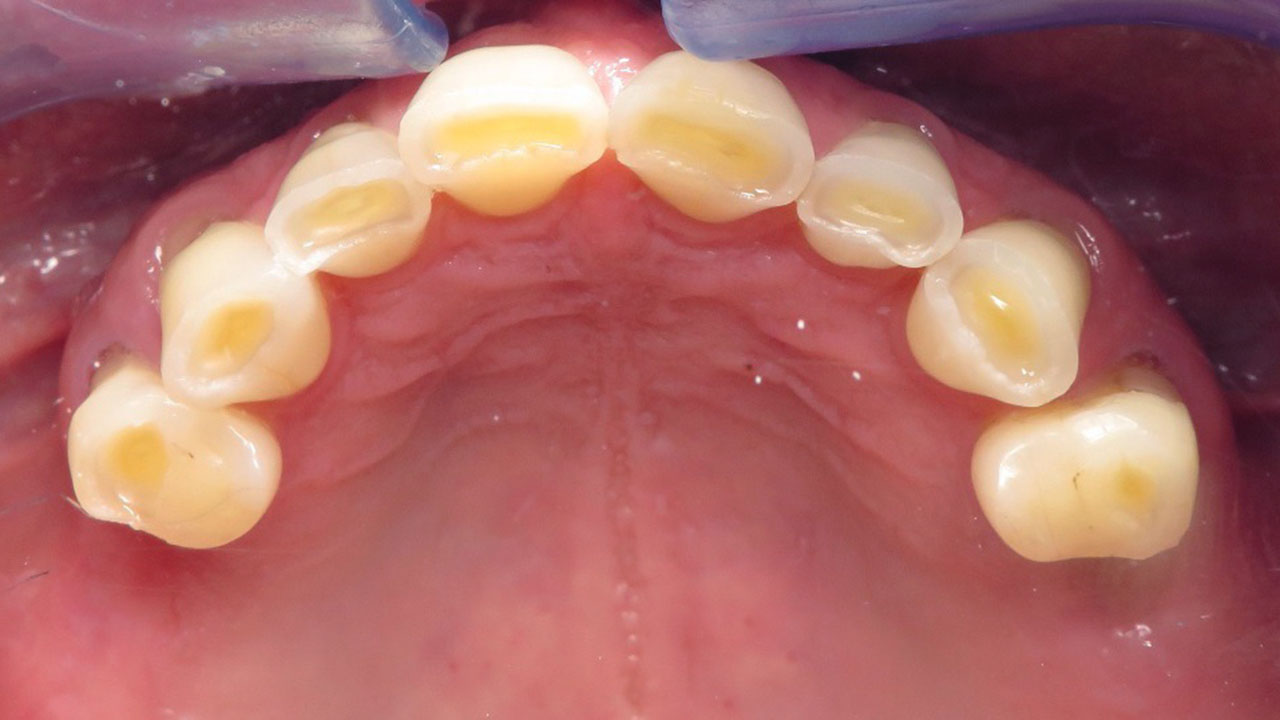

The patient was referred by his periodontist after being told that severe tooth grinding had worn his teeth down significantly and that he could lose his teeth if he did nothing to restore them.

Hopeless lower teeth were removed and the remaining teeth were restored with all-ceramic crowns to rebuild the bite and protect the worn dentition.

This patient was referred by his periodontist after severe tooth grinding had worn his teeth down significantly. He had already lost several teeth, and the remaining lower back teeth had a poor long-term prognosis if the bite was not restored.